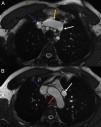

A RMC revelou dilatação biventricular e movimento anómalo do septo interventricular compatível com sobrecarga de volume. Nos planos axiais em balanced-steady state free precession (b-SSFP), observou-se veia anómala verticalmente orientada e lateral ao arco aórtico a comunicar com a veia inominada (Figura 1) e um seio coronário de dimensões normais.

A partir da angiografia, procedeu-se à reconstrução tridimensional do coração e grandes vasos, observando-se uma veia pulmonar anómala vertical a drenar na veia inominada (Figuras 2 e 3) condicionando drenagem venosa pulmonar anómala parcial do lobo pulmonar superior esquerdo (Qp:Qs de 1.4:1).

A. Angiografia (reconstrução tridimensional): projeção posterior do coração e grandes vasos; seta verde: veias pulmonares esquerdas; seta branca: veia pulmonar anómala vertical; seta amarela: veia inominada; seta azul: veia cava superior. B. Angiografia (reconstrução tridimensional): projeção lateral esquerda do coração e grandes vasos; seta branca: veia pulmonar anómala vertical.